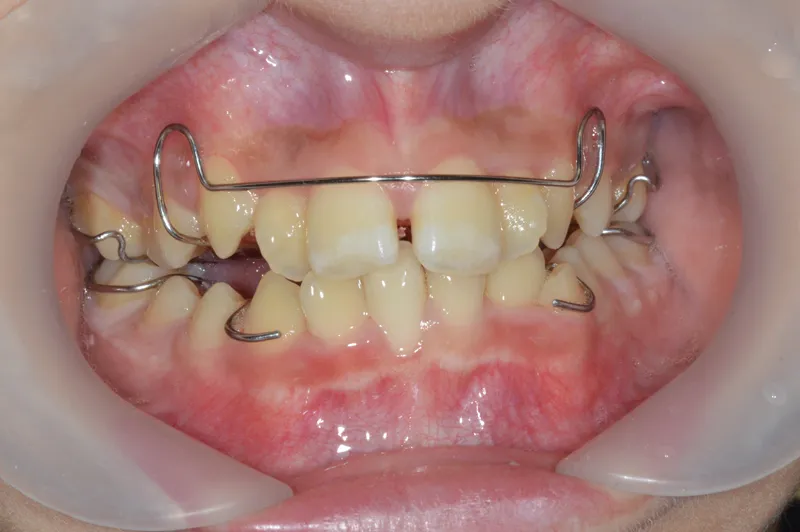

小児症例のご紹介-拡大床+前歯部分矯正+MFT

患者:11歳男児。

症状:歯並びがバラバラ、前歯がすいている、歯列弓の形その他

拡大床による歯列拡大

樹脂製の床とスクリューで構成された取り外し式装置を使用。

週1回スクリューを回して徐々に拡大。

使用期間は2年未満(開始年齢がやや遅いため短期で終了)。

前歯の部分矯正

拡大後も残った前歯のすき間と回転をワイヤーで整列。

前歯のすき間閉鎖と右上前歯の回転改善を確認。

MFTの継続により歯列弓形態も良好に成長。

Ⅰ期治療のみで十分に満足され、Ⅱ期治療は行わず定期健診中。